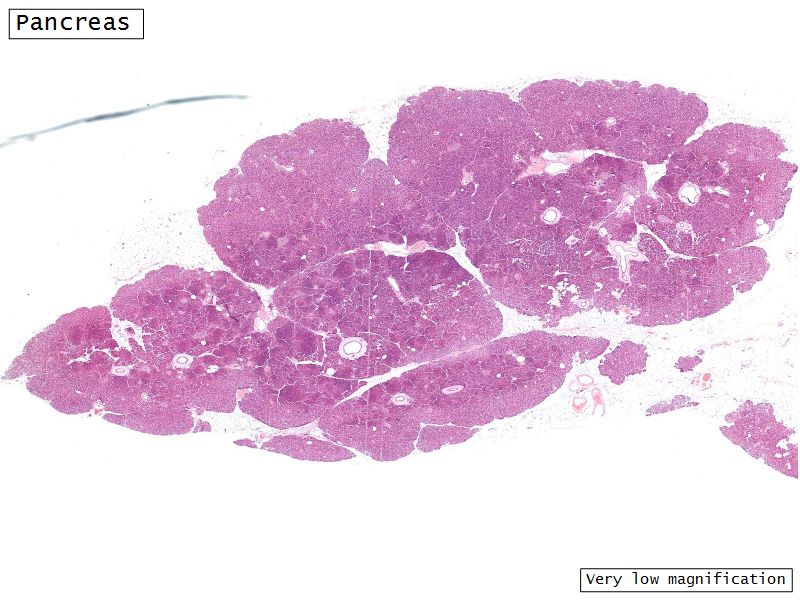

Glands of the Digestive System